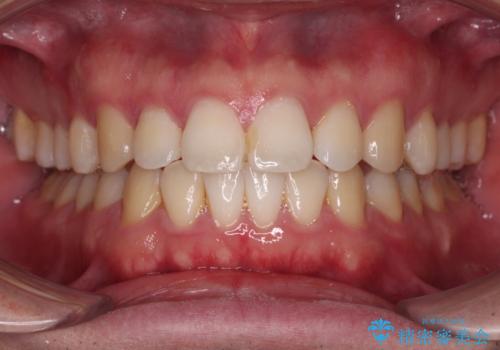

インビザラインで奥歯の咬み合わせと前歯のデコボコを改善

- 前歯のデコボコと奥歯の咬み合わせを気にして来院された患者様です。

前歯のデコボコはインビザラインで十分に対応可能と判断できましたが、咬合力が強いため、臼歯(特に右側)の交叉咬合はインビザライン単体では困難と思われました。

まずはインビザライン単体で矯正治療を開始し、交叉咬合が改善されない場合にはアンカースクリューなどの使用を検討することとしました。

インビザライン単体では右側の交叉咬合を解消することができなかったため、アンカースクリューを併用して咬合を改善させました。